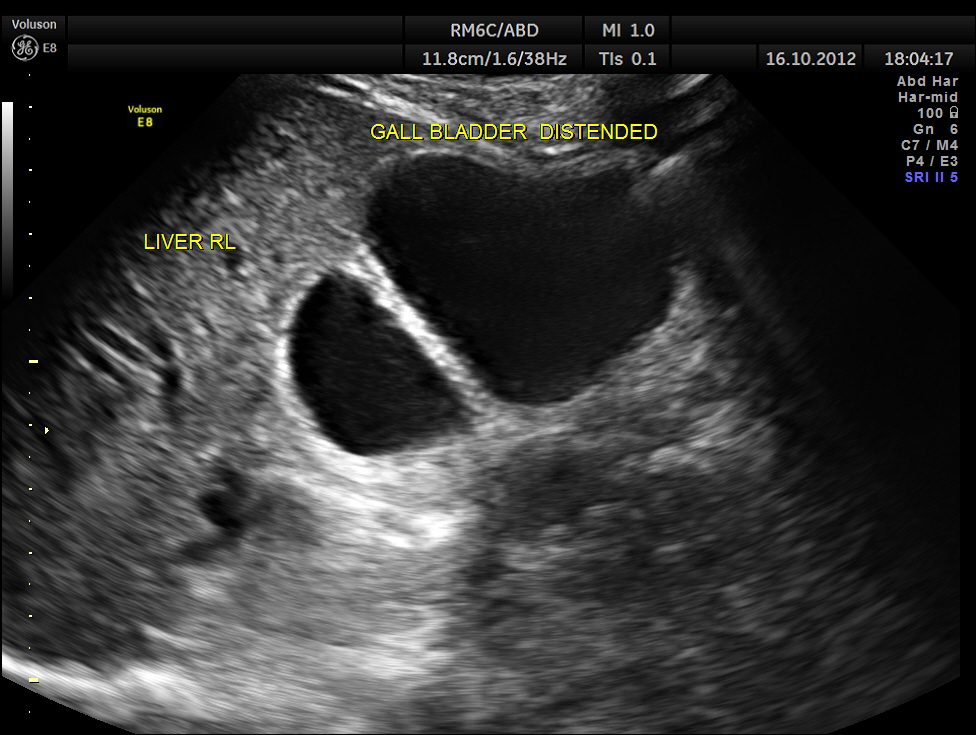

Courvoisier’s law (or Courvoisier syndrome, or Courvoisier’s sign or Courvoisier-Terrier’s sign) states that in the presence of an enlarged gallbladder which is nontender and accompanied with mild jaundice, the cause is unlikely to be gallstones. Usually, the term is used to describe the physical examination finding of the right-upper quadrant of the abdomen. This sign implicated possible malignancy of the gall bladder or pancreas and the swelling is unlikely due to gallstones.

This was a 55 year old man with history of jaundice and upper abdominal pain .